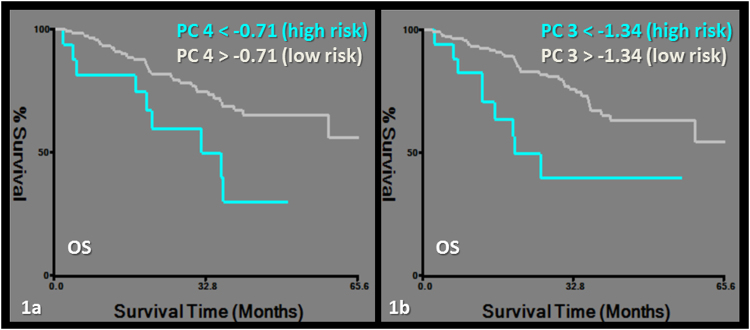

OS was predicted by a model including PC4 and PC3. Exclusively PET-derived features including first order (kurtosis and skewness), second order features (homogeneity and normalized entropy) and morphological features (morphology1 and 2) were grouped in PC4. Morphology1 assesses the area irregularity and morphology2 assesses the perimeter irregularity19. PC3 included exclusively CT-derived first order and morphological features (morphology2, asymmetry1 and 3) (Tables 2, 3, 4, Fig. 1). The asymmetry feature group measures the degree of bilateral symmetry exhibited by the lesion19.

Figure 1.

Kaplan-Meier survival curves for overall survival (OS). Subgroups of low and high risk were determined by a cut-off value of −0.71 for PC4 (logrank chi-square: 7.39, p = 0.09) (a) and −1.34 for PC3 (logrank chi-square: 8.92, p = 0.002) (b).